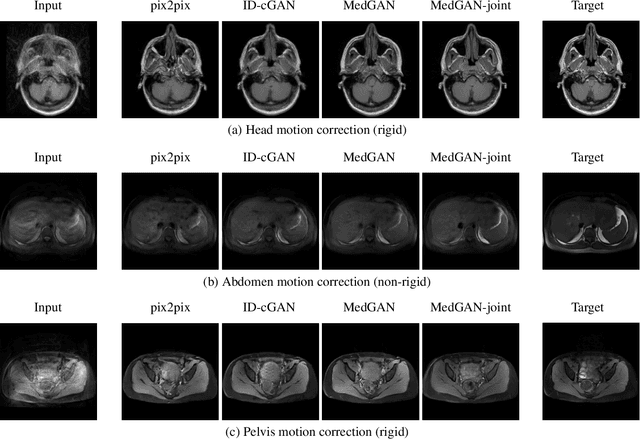

Abstract:Motion artifacts are a primary source of magnetic resonance (MR) image quality deterioration with strong repercussions on diagnostic performance. Currently, MR motion correction is carried out either prospectively, with the help of motion tracking systems, or retrospectively by mainly utilizing computationally expensive iterative algorithms. In this paper, we utilize a new adversarial framework, titled MedGAN, for the joint retrospective correction of rigid and non-rigid motion artifacts in different body regions and without the need for a reference image. MedGAN utilizes a unique combination of non-adversarial losses and a new generator architecture to capture the textures and fine-detailed structures of the desired artifact-free MR images. Quantitative and qualitative comparisons with other adversarial techniques have illustrated the proposed model performance.

Abstract:Image-to-image translation is considered a next frontier in the field of medical image analysis, with numerous potential applications. However, recent advances in this field offer individualized solutions by utilizing specialized architectures which are task specific or by suffering from limited capacities and thus requiring refinement through non end-to-end training. In this paper, we propose a novel general purpose framework for medical image-to-image translation, titled MedGAN, which operates in an end-to-end manner on the image level. MedGAN builds upon recent advances in the field of generative adversarial networks(GANs) by combining the adversarial framework with a unique combination of non-adversarial losses which captures the high and low frequency components of the desired target modality. Namely, we utilize a discriminator network as a trainable feature extractor which penalizes the discrepancy between the translated medical images and the desired modalities in the pixel and perceptual sense. Moreover, style-transfer losses are utilized to match the textures and fine-structures of the desired target images to the outputs. Additionally, we present a novel generator architecture, titled CasNet, which enhances the sharpness of the translated medical outputs through progressive refinement via encoder decoder pairs. To demonstrate the effectiveness of our approach, we apply MedGAN on three novel and challenging applications: PET-CT translation, correction of MR motion artefacts and PET image denoising. Qualitative and quantitative comparisons with state-of-the-art techniques have emphasized the superior performance of the proposed framework. MedGAN can be directly applied as a general framework for future medical translation tasks.